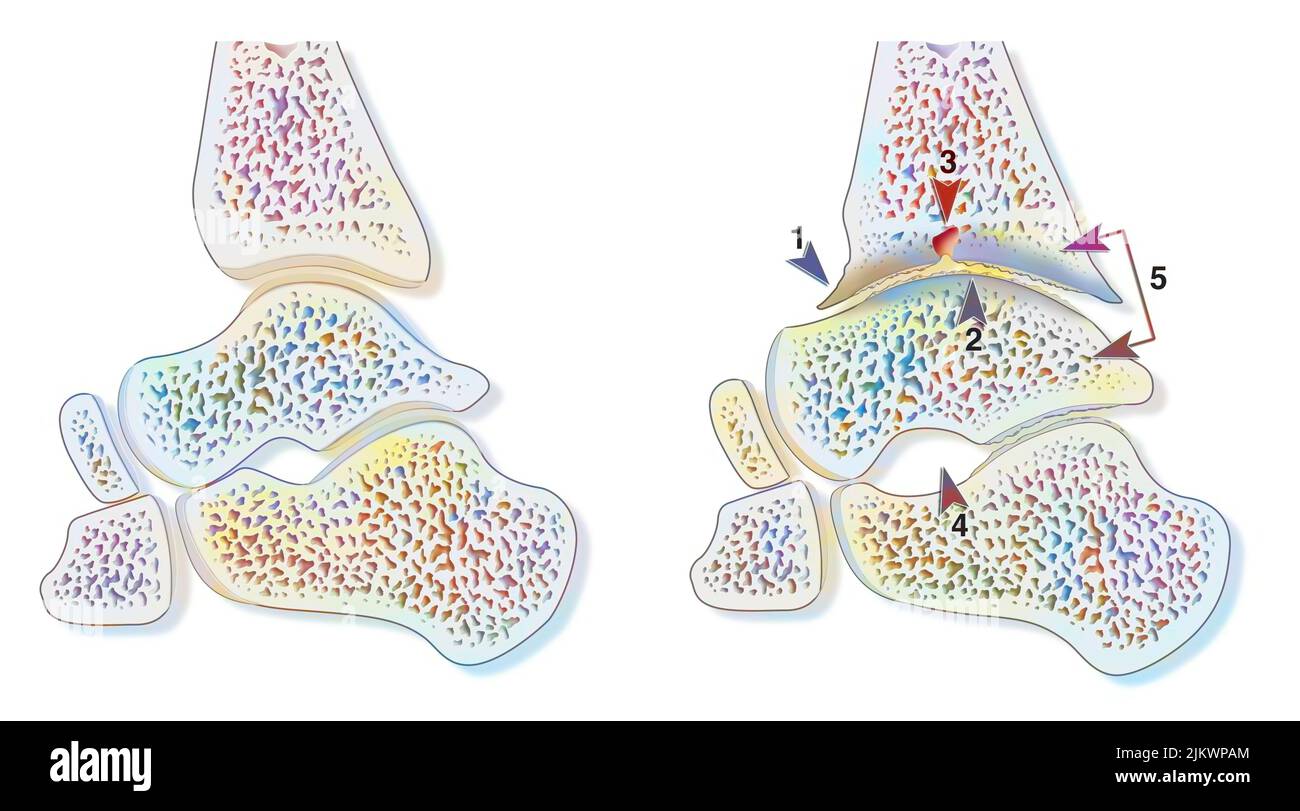

RFRMP153–Onychomycose ou mycose des ongles infection ou tinea unguium comme un ongle de pied infecté ou d'orteil endommagé avec l'anatomie humaine saine et malsaine.

RFT3975F–Orteil fongiques infectés et les pieds infection ou onychomycosisor tinea unguium comme maladie pied ongle endommagé avec l'anatomie humaine malsaine.

RFRMWCF2–L'infection fongiques des ongles et onychomycosisor tinea unguium comme un ongle de pied infecté ou d'orteil endommagé avec l'anatomie humaine saine et malsaine.